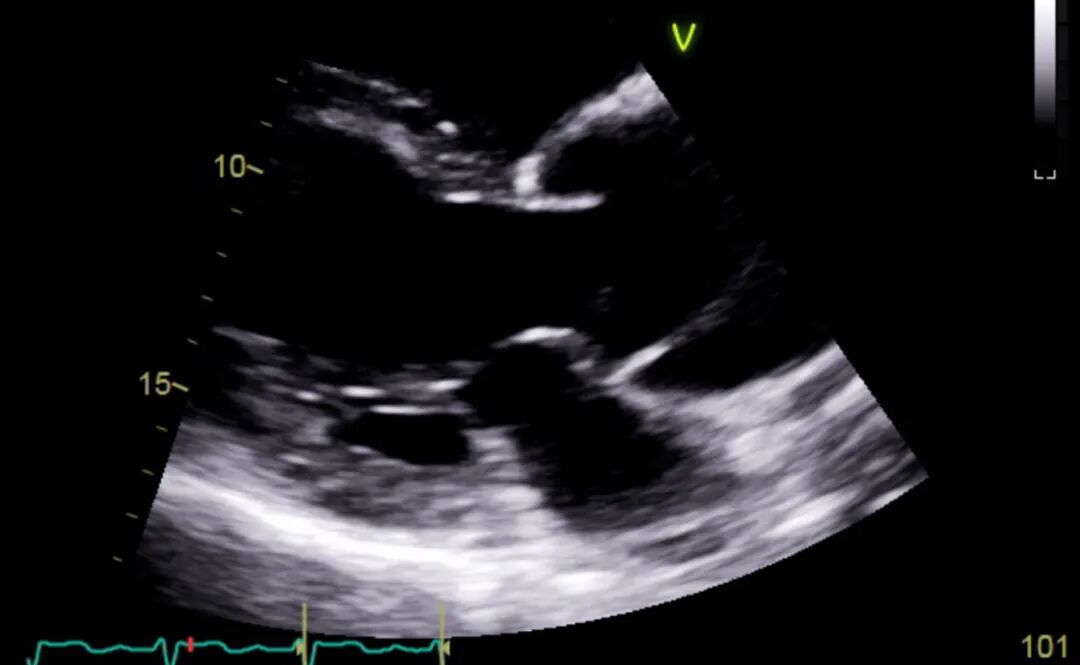

图3 TTE胸骨旁长轴切面

TTE显示升主动脉内夹层内膜片,位于主动脉瓣叶上方。同时可见升主动脉扩张。